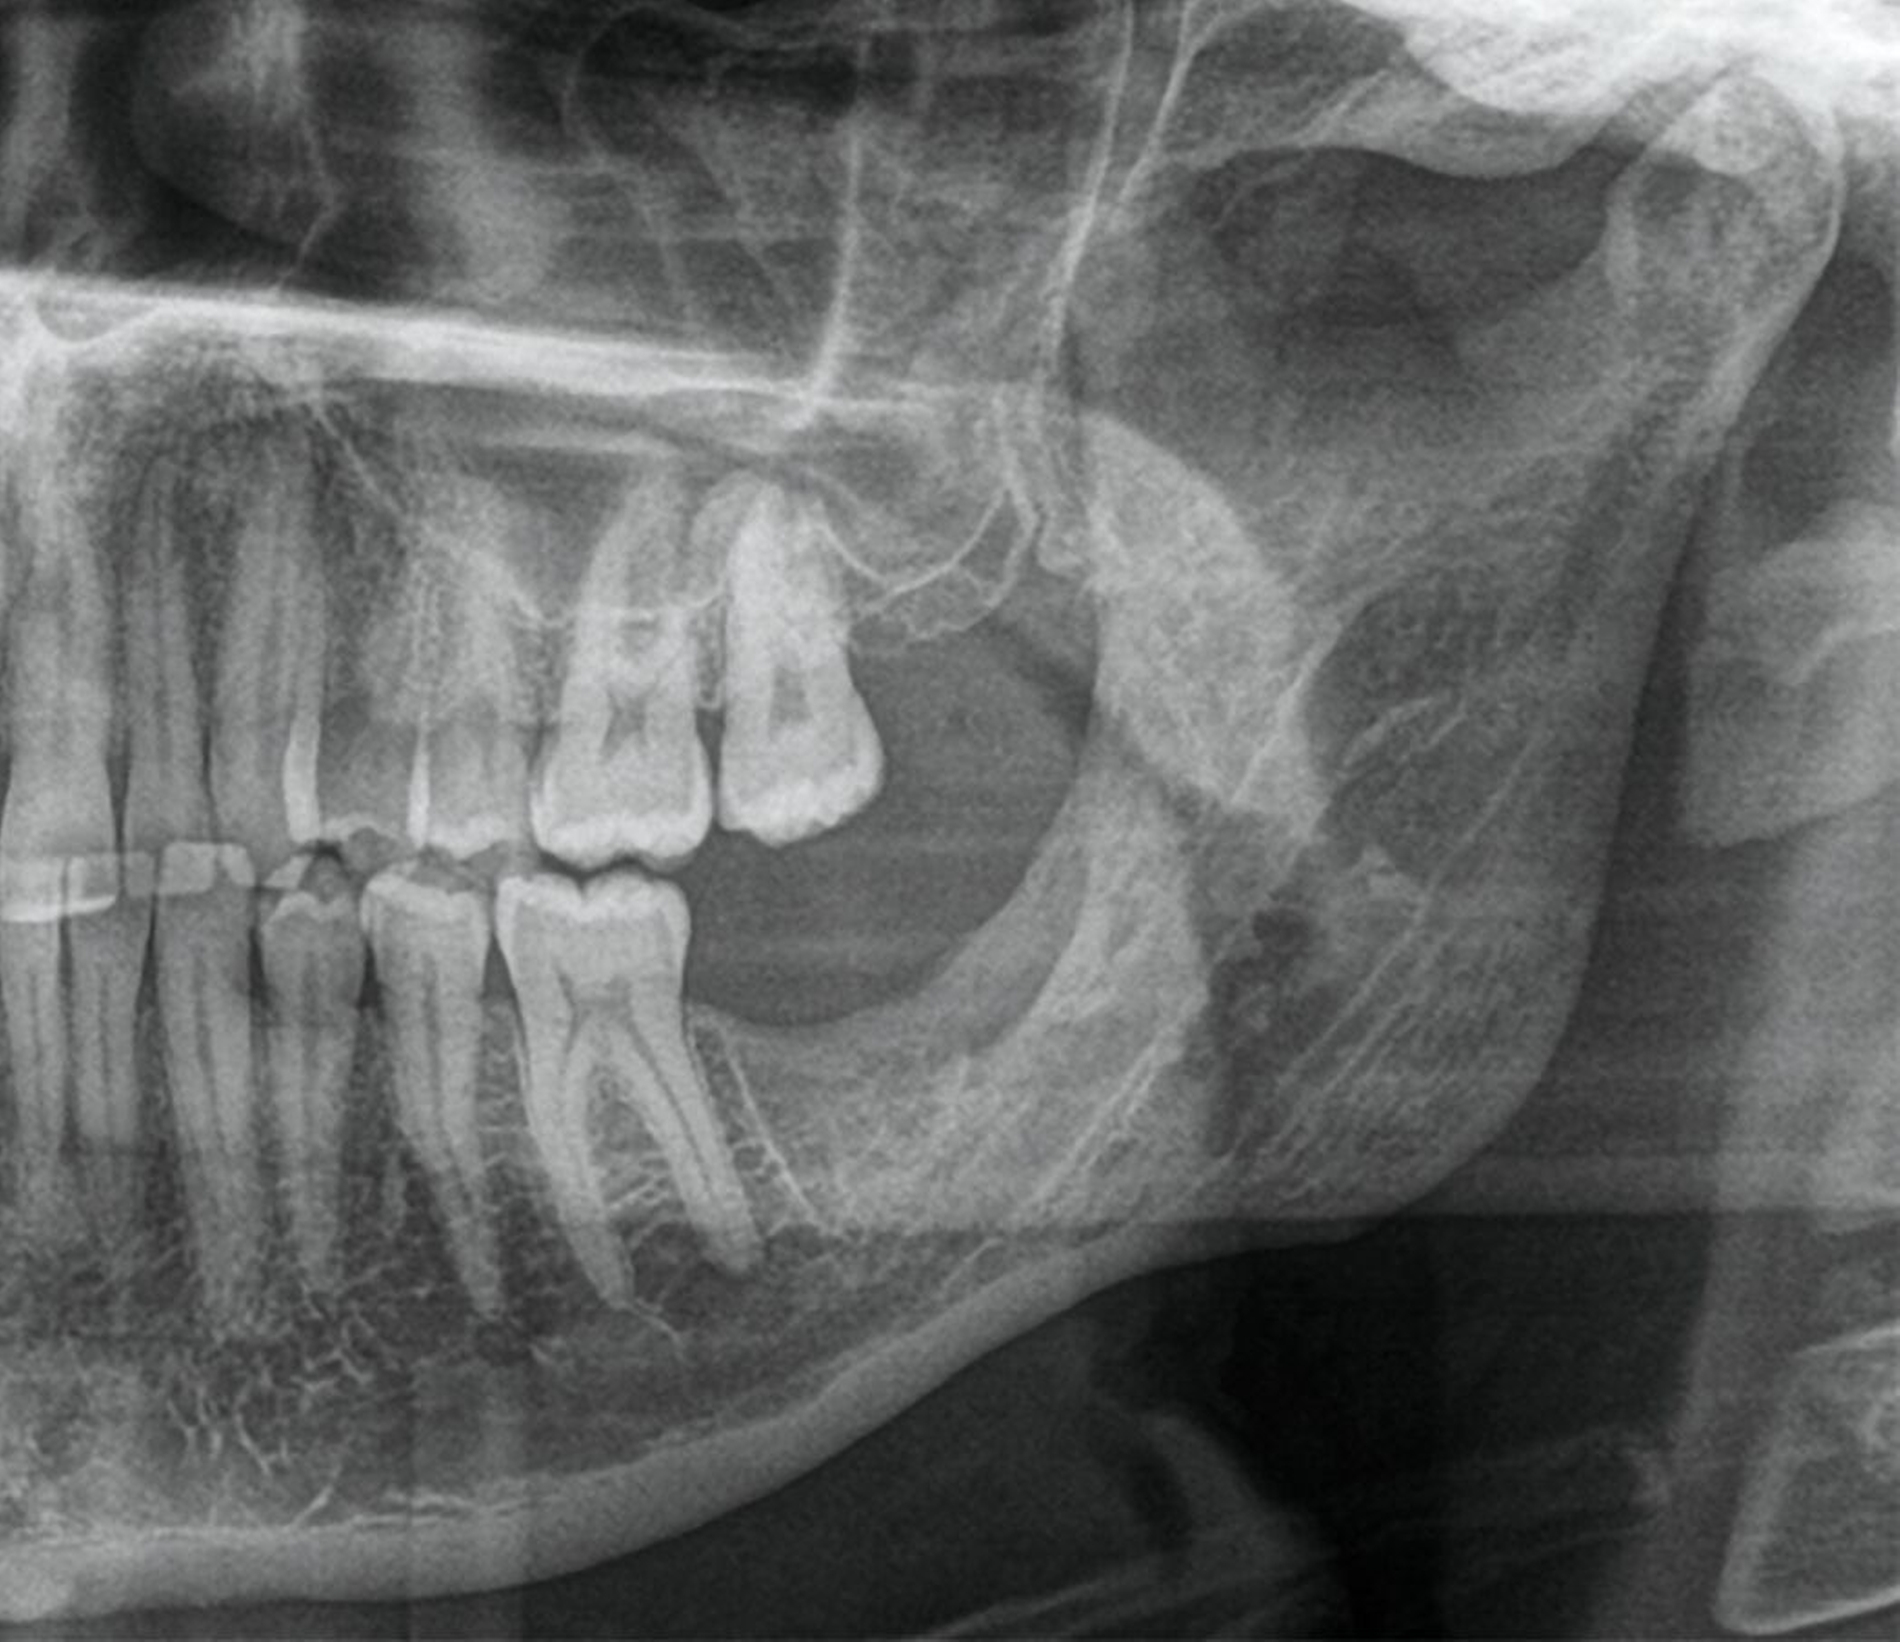

Die digitale Volumentomografie (DVT) ergab eine mehrkammerige, radioluzente Raumforderung, die sich bei erhaltener Kortikalis von der mesialen Wurzel des Zahnes 37 bis in den aufsteigenden Ast des Ramus mandibulae erstreckte (Abbildungen 1 und 2). Aufgrund der Morphologie bestand der Verdacht auf einen keratozystischen odontogenen Tumor, differenzialdiagnostisch auf andere odontogene Tumoren. Nach Aufklärung wurden die Extraktion des nicht erhaltungswürdigen Zahnes 37 sowie die Zystektomie geplant und zwei Wochen später in Intubationsnarkose durchgeführt.

Die seitdem halbjährlich durchgeführten Nachkontrollen zeigen klinisch reizlose Verhältnisse und einen beschwerdefreien Patienten. Radiologisch fand sich eine fortschreitende knöcherne Ausheilung ohne Rezidivhinweise, wie in den Verlaufskontrollen unmittelbar postoperativ, nach einem Jahr und nach zwei Jahren dargestellt (Abbildung 5). Angesichts möglicher Spätrezidive wird die langfristige Nachsorge fortgeführt.